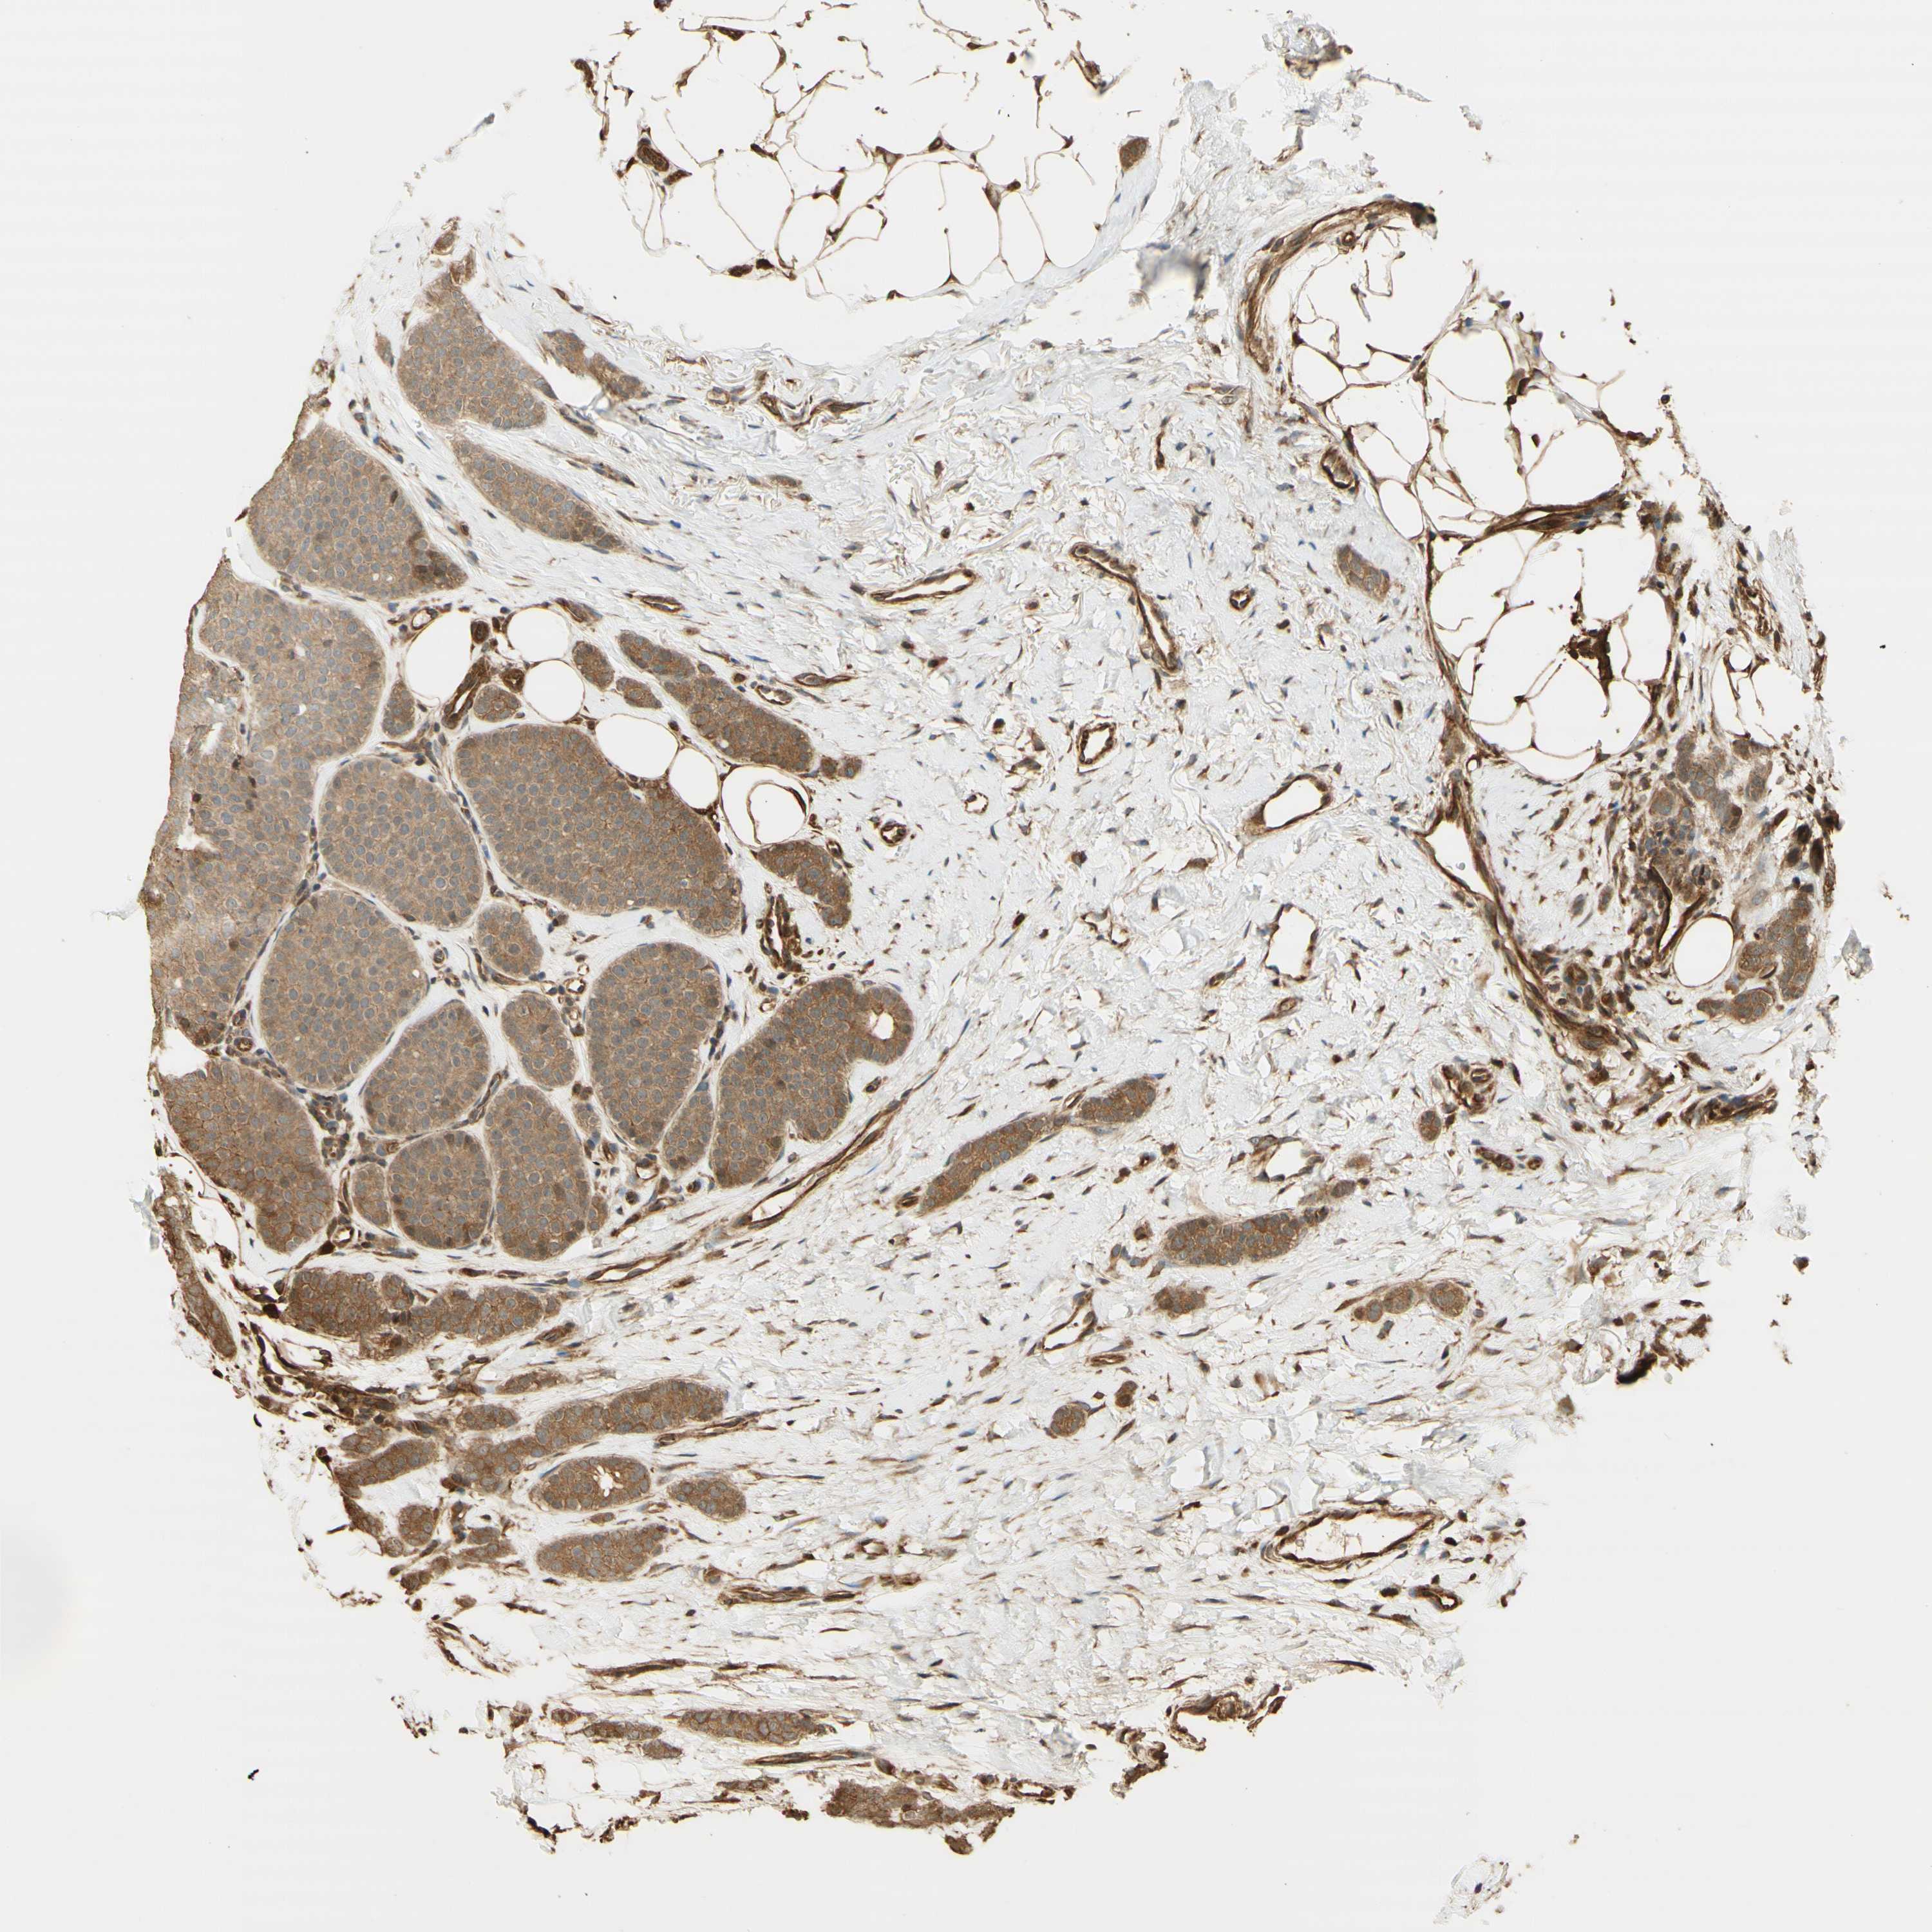

CANCER BREAST CANCER Show tissue menu

BRCA TCGA BRCA VALIDATION PROTEIN EXPRESSION

ANTIBODIES

AND

VALIDATION